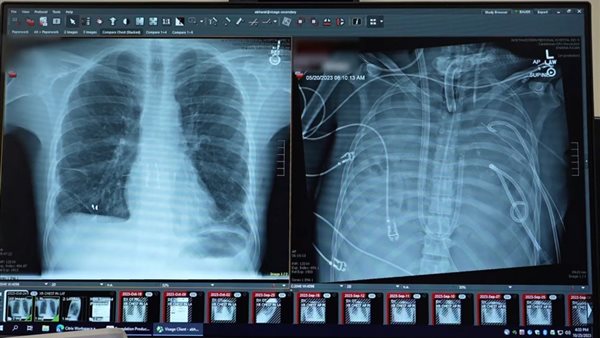

وداهمته العدوى، وهو المصطلح الطبي الذي يشير إلى عدم قدرة الجسم على التخلص منها، فتآكلت رئتاه بفعل البكتيريا، وتسببت في المزيد والمزيد من القيح، وأصيب بسكتة قلبية مميتة في المستشفى لكن توصل الجراحون إلى خطة لاستبدال رئتيه، وبعد أن استنزفوا كل دمه خلال الجراحة، وتم استخدام زراعة الثديين لإبقاء القلب مباشرة في منتصف صدره، وفي الوقت نفسه، استخدام رئتين صناعيتين لإبقائه يتنفس خلال إزالة أعضائه المصابة بالمرض.

وتم إجراء عملية زرع رئة له في غضون أيام بفضل متبرع في مركز قريب، ويتعافى ديفي الآن كمريض خارجي، مع العلاج والاختبارات المنتظمة، وأكد الخبراء أن التدخين الإلكتروني لعب دورًا كبيرًا في مرض ديفي، لأنه كان يتمتع بصحة جيدة وبلياقة بدنية.